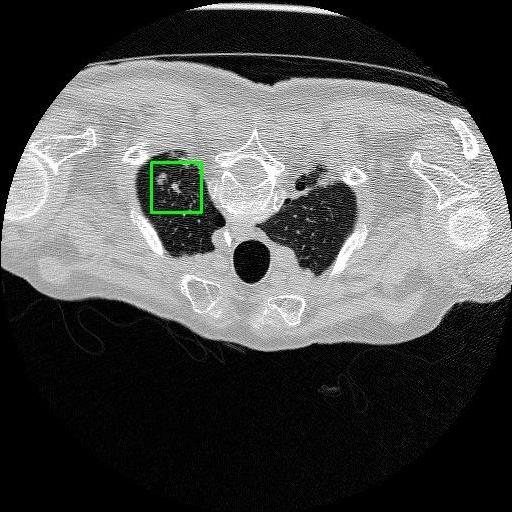

We developed an AI-based system using deep learning models for analyzing lung CT scans to detect and classify pulmonary nodules. We chose the YOLOv11 architecture for its enhanced object detection capability and adapted it specifically for medical imaging, incorporating pixel-level precision and severity classification.

Classification into three severity levels with colored bounding boxes.

Designed a severity classification system that categorizes nodules into null, moderate, and severe using colored bounding boxes, assisting in rapid clinical decision-making.